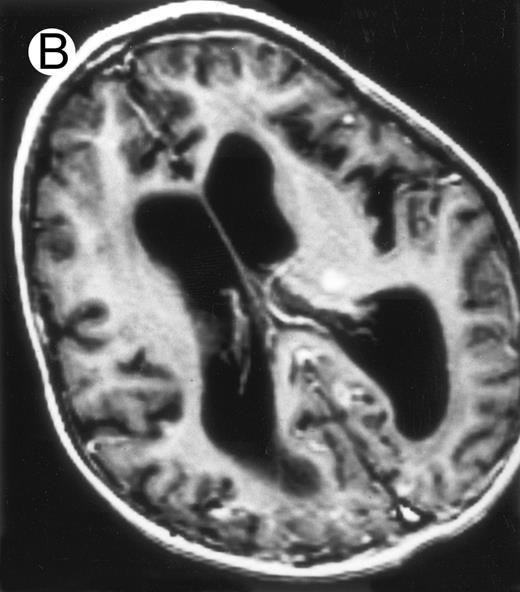

Together, 19 patients had primary severe CNS disease progression or CNS relapse (Fig 1). Three of 19 had a CNS relapse characterized by meningitis only. Neurological symptoms occurred in 16 of these 19 patients (9 from the onset and 7 after the initial meningitis) (Fig 1). No clinical or neuroradiological difference was detected between the patients who developed neurological symptoms as the initial CNS manifestation or after initial meningitis (Table 1). The occurrence of these neurological manifestations marked a turning point in the evolution of the disease, as chemotherapy led to an improvement of the neurological symptoms in only three patients despite the use of intensive treatment by MTX IT. In these three patients, neurological sequelae persisted after the first symptoms and a relapse occurred within 3 to 10 months. Brain imaging was repeated during chemotherapy for four patients with progression of the CNS disease: in three patients, a severe brain atrophy developed (Fig 3A and B) and in the last patient who initially had contrast enhancement in cerebellar white matter, a cerebellum parenchymal loss was observed (Fig 2C). All of these 19 patients treated by chemotherapy only (n = 15) died during a last episode of coma and brain stem symptoms associated with a systemic hemophagocytic syndrome, 6 ± 6 months after the first neurological symptom (irrespective of the age at this first event). Four of these 19 patients were transplanted (one patient received an HLA-identical BMT, three an HLA-partially identical BMT). Median delay between diagnosis and BMT was 14 months (range, 2 to 20 months). All of these four patients died of BMT-related toxicity and/or disease progression.

Evolution of brain lesions during HLH. (A) MRI of a 41/2-year-old girl showing focal white matter hypersignal on T2-weighted images. (B) MRI of the same child 1 year later with an important atrophy of both the white matter and the cortices.